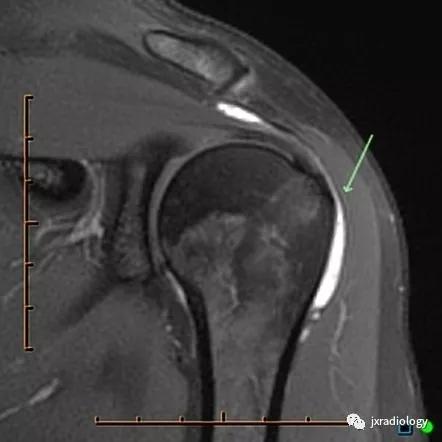

图1:肩峰下 - 三角肌下滑囊(subacromial-subdeltoid bursa)